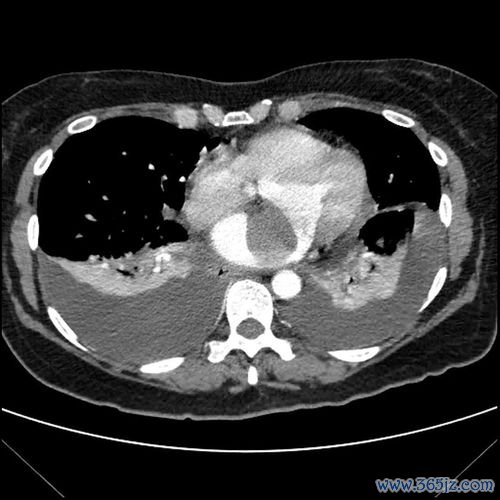

肝癌-乙肝携带者多年不复查,肚子胀发现肝癌破裂出血

引言:被忽视的“小毛病”与致命的转折 在快节奏的现代生活中,许多人都背负着健康“历史问题”前行,其中慢性乙型肝炎病毒(HBV)携带者是一个庞大的群体。对于部分携带者而言,由于早期可能没有明显症状,加之对疾病进展的轻视或对长期服药的顾虑,定期复查常常被置于次要位置,甚至被完全遗忘。肝脏是一个“沉默的器官”,当其内的隐患悄然滋长、最终爆发时,往往已酿成无法挽回的...